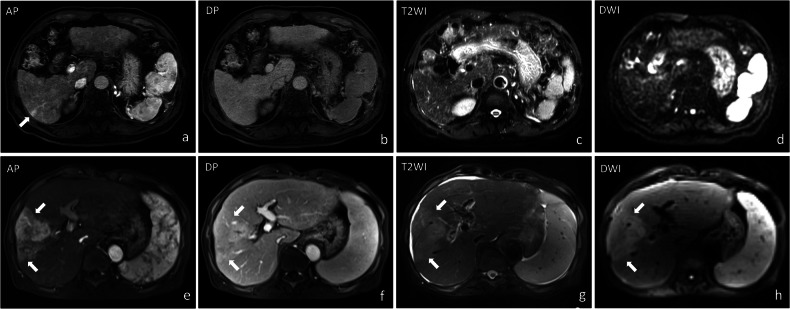

{"title":"Transient hepatic intensity differences: correlations with treatment outcomes and adverse events following DEB-TACE in hepatocellular carcinoma.","authors":"Noble Chibuike Opara, Shuwei Zhou, Weilang Wang, Shuhang Zhang, Xunjun Chen, Shenghong Ju, Yuan-Cheng Wang","doi":"10.1186/s13244-025-02041-2","DOIUrl":null,"url":null,"abstract":"<p><strong>Background: </strong>Transient hepatic intensity differences (THID) on MRI are commonly observed in hepatocellular carcinoma (HCC) patients following drug-eluting bead transarterial chemoembolization (DEB-TACE). We evaluated the association between THID, treatment outcomes, and adverse events in HCC patients treated with DEB-TACE.</p><p><strong>Materials and methods: </strong>This retrospective analysis included data from a prospective study conducted with 102 consecutive HCC patients treated with DEB-TACE between December 2017 and December 2020. The chi-square test assessed correlations between THID and adverse events, including biliary injury, intrahepatic metastasis, and portal venous thrombosis. Kaplan-Meier method evaluated overall survival (OS) and progression-free survival (PFS), with log-rank tests comparing THID complexity (simple vs complex) and severity (mild, moderate, and severe). Logistic regression identified factors associated with THID development.</p><p><strong>Results: </strong>Among the 102 HCC patients, 74 (72.5%) developed THID after DEB-TACE. Patients with THID had significantly higher rates of biliary injury (47% vs 14.3%, p = 0.002) and intrahepatic metastasis (25.7% vs 7.1%, p = 0.030). Complex THID was associated with worse PFS (p = 0.024). Moderate-to-severe THID had worse OS (p = 0.019) and PFS (p = 0.038). Factors associated with THID development included a higher tumor burden, baseline THID, and Child-Pugh class A.</p><p><strong>Conclusion: </strong>THID correlates with an increased risk of biliary injury and intrahepatic metastasis and is associated with worse OS and PFS in HCC patients following DEB-TACE.</p><p><strong>Critical relevance statement: </strong>THID development after DEB-TACE correlates with higher incidence of biliary injury, intrahepatic metastasis, and worse OS/PFS, emphasizing its potential as a critical imaging biomarker. This study advances clinical radiology by highlighting THID as an important factor in treatment outcomes.</p><p><strong>Key points: </strong>THID after drug-eluting bead transcatheter arterial chemoembolization correlates with treatment outcomes and adverse events in HCC. THID correlates with higher biliary injury, intrahepatic metastasis, and reduced survival rates. Complex or severe THID correlates with poorer survival in HCC patients.</p>","PeriodicalId":13639,"journal":{"name":"Insights into Imaging","volume":"16 1","pages":"164"},"PeriodicalIF":4.5000,"publicationDate":"2025-08-01","publicationTypes":"Journal Article","fieldsOfStudy":null,"isOpenAccess":false,"openAccessPdf":"https://www.ncbi.nlm.nih.gov/pmc/articles/PMC12316659/pdf/","citationCount":"0","resultStr":null,"platform":"Semanticscholar","paperid":null,"PeriodicalName":"Insights into Imaging","FirstCategoryId":"3","ListUrlMain":"https://doi.org/10.1186/s13244-025-02041-2","RegionNum":2,"RegionCategory":"医学","ArticlePicture":[],"TitleCN":null,"AbstractTextCN":null,"PMCID":null,"EPubDate":"","PubModel":"","JCR":"Q1","JCRName":"RADIOLOGY, NUCLEAR MEDICINE & MEDICAL IMAGING","Score":null,"Total":0}

Results: Among the 102 HCC patients, 74 (72.5%) developed THID after DEB-TACE. Patients with THID had significantly higher rates of biliary injury (47% vs 14.3%, p = 0.002) and intrahepatic metastasis (25.7% vs 7.1%, p = 0.030). Complex THID was associated with worse PFS (p = 0.024). Moderate-to-severe THID had worse OS (p = 0.019) and PFS (p = 0.038). Factors associated with THID development included a higher tumor burden, baseline THID, and Child-Pugh class A.

Conclusion: THID correlates with an increased risk of biliary injury and intrahepatic metastasis and is associated with worse OS and PFS in HCC patients following DEB-TACE.